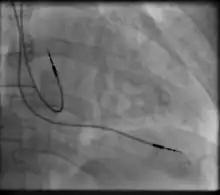

Permanent pacing with an implantable pacemaker involves transvenous placement of one or more pacing electrodes within a chamber, or chambers, of the heart, while the pacemaker is implanted under the skin below the clavicle. The procedure is performed by incision of a suitable vein into which the electrode lead is inserted and passed along the vein, through the valve of the heart, until positioned in the chamber. The procedure is facilitated by fluoroscopy which enables the physician to view the passage of the electrode lead. After satisfactory lodgement of the electrode is confirmed, the opposite end of the electrode lead is connected to the pacemaker generator.

A pacemaker may be implanted whilst a person is awake using local anesthetic to numb the skin with or without sedation, or asleep using a general anesthetic.[25] An antibiotic is usually given to reduce the risk of infection.[25] Pacemakers are generally implanted in the front of the chest in the region of the left or right shoulder. The skin is prepared by clipping or shaving any hair over the implant site before cleaning the skin with a disinfectant such as chlorhexidine. An incision is made below the collar bone and a space or pocket is created under the skin to house the pacemaker generator. This pocket is usually created just above the pectoralis major muscle (prepectoral), but in some cases the device may be inserted beneath the muscle (submuscular).[26] The lead or leads are fed into the heart through a large vein guided by X-ray imaging (fluoroscopy). The tips of the leads may be positioned within the right ventricle, the right atrium, or the coronary sinus, depending on the type of pacemaker required.[25] Surgery is typically completed within 30 to 90 minutes. Following implantation, the surgical wound should be kept clean and dry until it has healed. Some movements of the shoulder within a few weeks of insertion carry a risk of dislodging the pacemaker leads.[25]